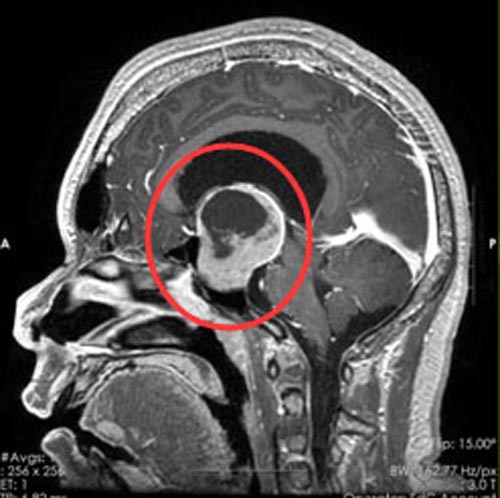

直到最近出现了头痛呕吐,黄女士这才在家人的陪伴下来到广东三九脑科医院综合神经外科,脑部核磁共振检查提示“鞍区占位”。

发现是鞍区肿瘤后,经患者及家属同意,鲁明副院长主刀行“内镜经鼻蝶鞍区占位切除术”,顺利全切除了肿瘤。术后病理证实为“生长激素型垂体瘤”。